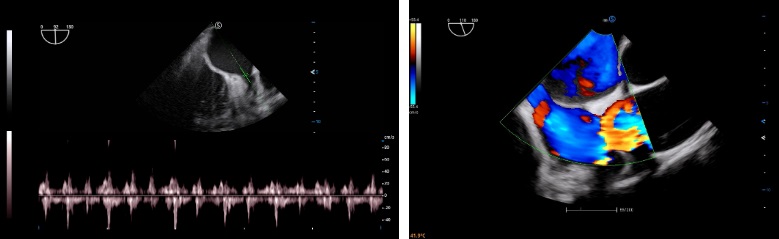

- Category: Color Doppler

Pixel Echo Zone (PEZ)

During wide band imaging processing, the system automatically collects echo information by larger processing zone to enhance acquisition efficiency and computing speed. Increased image frame rate facilitates a better and faster diagnostic experience.

Target Focus

The image focus in near and far field requires different signal intensity. This upgraded technology provides automatic compensation in signal transmission to further improves focus accuracy and image uniformity in the entire image area.

Dynamic analysis of Doppler echo spectrum enables the system to capture effective signal in both low and high frequency range. Precise control and fusion of these signals contribute to optimal image with better combination of resolution and penetration.

This technology traces and analyzes image information on multi-direction to suppress artifacts that come from tissue movement and rotation. The image quality and real-time capability are greatly boosted in special compound imaging.

Auto EF

Cardiac function evaluation requires accuracy and speed as various calculations needs to be made. Auto EF, based on speckle tracking technology, acquires 2D EF and volumes within streamlined workflow.

Auto SG

Global and regional myocardial function can be evaluated by Auto SG, an automatic quantitative assessment tool.

Crystal Purity Transducer

Equipped with the crystal purity transducer, Apogee 5800 Ace conducts superb scanning on cardiac diseases such as CHD (congenital heart disease).

TEE

As a minimally invasive diagnostic way and real-time cardiac imaging device, TEE (Transesophageal echocardiogram) ultrasound is capable of providing additional diagnostic information.